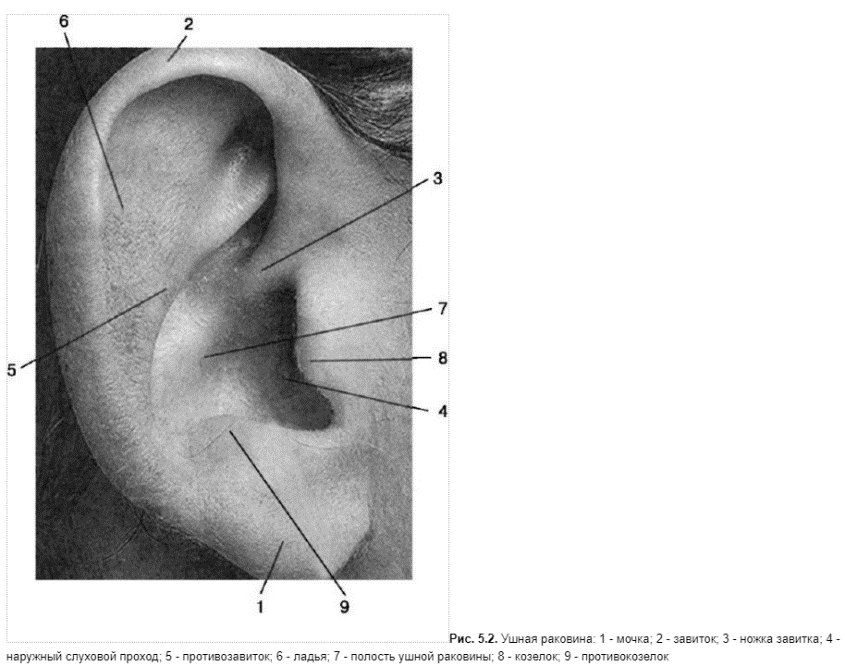

КТ анатомия сосцевидного отростка: особенности и показания